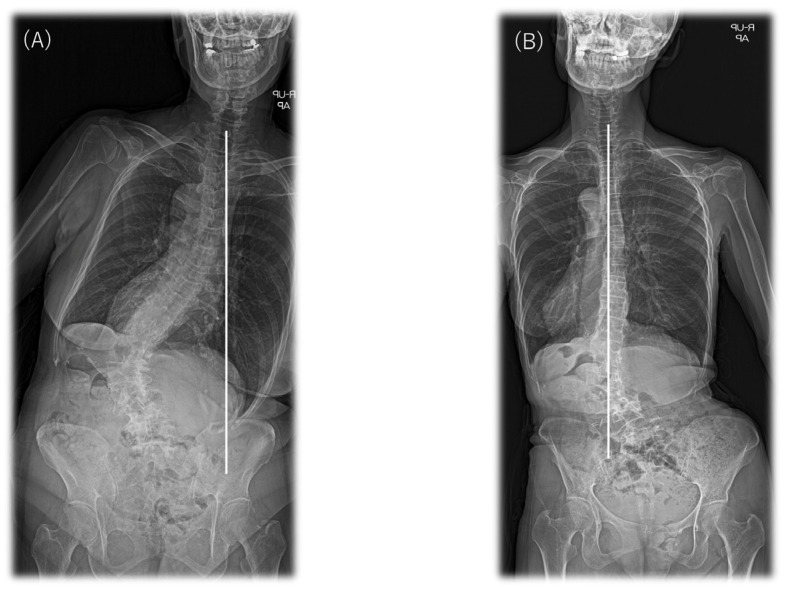

This retrospective observational study evaluated improvement in coronal malalignment (CM) after anteroposterior staged surgery using lateral lumbar interbody fusion (LLIF) in patients with coronal lumbar curve adult spinal deformity (ASD). Sixty patients with ASD underwent surgery; 34 had SRS–Schwab type L lumbar curve. Patients with a coronal balance distance (CBD) ≥20 mm were diagnosed with CM. Using the Obeid CM classification, we classified the preoperative coronal pattern as concave CM (type 1) or convex CM (type 2). Demographic, surgical, and radiological parameters were compared. Whole-spine standing radiographs were assessed preoperatively and postoperatively. Twenty-three patients had type 1A, six had type 2A, five had no CM, and none had type 1B or 2B according to the Obeid CM classification. Compared with patients with Obeid type 1A, those with Obeid type 2A had significantly higher preoperative and postoperative coronal L4 tilts and a smaller change in corrected CBD (Δ|CBD|) (76.6 mm vs. 24.1 mm, p < 0.001). At the final follow-up, 58.6% (17/29 patients) of patients with SRS–Schwab type L CM showed improvement after corrective fusion using LLIF. Although the difference was not statistically significant, CM improved in 69.6% (16/23 patients) of patients with Obeid type 1A type but only 16.7% (1/6 patients) of those with Obeid type 2A type (p = 0.056). CM was more likely to remain after anteroposterior staged surgery using LLIF in patients with preoperative Obeid type 2A ASD.

The data comprised radiological and demographic information and surgical parameters. All patients underwent full-length anteroposterior and lateral standing X-rays. Radiographs were evaluated for coronal alignment and sagittal spinopelvic parameters. These measures were used to classify each patient according to the SRS–Schwab classification. Briefly, sagittal measurements included (1) LL; (2) TK (T5–T12); (3) PT; (4) pelvic incidence (PI); (5) sacral slope; (6) PI–LL; and (7) SVA. The following parameters were measured in the coronal plane. Coronal balance distance (CBD) was defined as the horizontal distance between the C7 PL and the central sacral vertical line. C7 PL shifted to the right and was defined as positive and to the left as negative. Δ|CBD| was calculated from postoperative CBD−preoperative CBD and calculated as its absolute value. That is, |CBD| is represented as a positive. For example, if the preoperative CBD was 70.1 mm and the postoperative CBD was −20.3 mm, −20.3 − 70.1 = −90.4 mm and Δ|CBD| = 90.4mm. The major Cobb angles were defined as the angle between the superior end plate of the most tilted vertebra cranially and the inferior end plate of the most tilted vertebra caudally. L4 coronal tilt and L5 tilt were defined as the angle between the superior end plate of L4 or L5 and the horizontal line [ref. 22]. We also evaluated each patient’s curve flexibility in the coronal plane using side bending and traction radiographs. The SRS–Schwab system includes an assessment of the coronal curve type and sagittal modifiers [ref. 17]. The coronal curve type is based on the spine location and Cobb angle (>30°) of the scoliotic curves and is classified as follows: (1) curve type T: thoracic only; the thoracic major curve of >30° at the apical level of T9 or higher; (2) curve type L: thoracolumbar/lumbar only; isolated thoracolumbar or lumbar curve > 30° at the apical level of T10 or lower; (3) curve type D: a double major curve with thoracic and thoracolumbar/lumbar curve of >30°; and (4) curve type N: normal; no definite coronal deformity (all coronal curves < 30°). After classifying by type of coronary curve, we included patients with type L curves in this study. All patients were subgrouped according to their preoperative coronal alignment as defined by Obeid et al. according to the distance between their C7 PL and their central sacral vertical line [ref. 9]. The Obeid CM classification system first divides the patients with CM into two main types according to their CM deformity patterns. Concave CM (type 1) is defined as CM with a coronal T1 PL falling at the side of the concavity of the main coronal curve. By contrast, convex CM (type 2) is defined as CM with a coronal T1 PL falling at the side of the convexity of the main coronal curve > 20 mm (Figure 1).

Patients can be subtyped further as type 1A, having the main curve apex between T12 and L4, and type 1B, having the apex above T12. Type 1A1 is flexible, and type 1A2 is rigid. Type 2A has the apex of the main curve between T12 and L4, whereas type 2B has the apex below L4. Type 2A1 has a normal lumbosacral junction, and type 2A2 has a degenerative lumbosacral junction. Patients with no CM are defined as having a C7 PL within 20 mm of the CBD. Pre- and the postoperative coronal imbalance were defined as |CBD| ≥ 20 mm [ref. 9]. We defined the proximal junctional angle (PJA) as the sagittal Cobb angle between the inferior endplate of UIV and the superior endplate of UIV + 2. For PJA, the value at the time of the last observation was used, but for patients with proximal junctional failure (PJF), the value at the time of PJF observation was used [ref. 20,ref. 21,ref. 23]. These data were then compared between the patients with Obeid type 1A and those with Obeid type 2A CM.